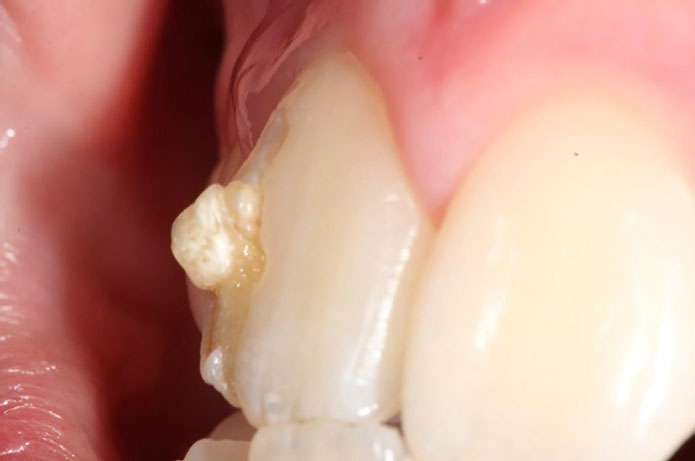

Czym jest elektrokoagulacja? Elektrokoagulacja to zabieg polegający na kontrolowanym wykorzystaniu prądu elektrycznego w celu zamknięcia naczyń krwionośnych oraz usunięcia zmienionych tkanek. W stomatologii metoda ta znajduje zastosowanie przede wszystkim w chirurgii i periodontologii. Stomatolog w nowoczesnej klinika stomatologiczna Kraków wykorzystuje…